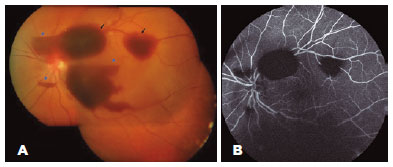

Ophthalmic examination revealed a best-corrected visual acuity of 20/125 in the LE, without any changes in the anterior segment. The intraocular pressure was normal. Fundus examination of the LE revealed mild vitreous and multiple large preretinal hemorrhages in the macular area (Figure 1A). The right eye (RE) examination result was normal.

OCT (Spectralis Heidelberg Engineering, Heidelberg, Germany) of the LE revealed multiple subhyaloid and sub-internal limiting membrane (ILM) hemorrhages of variable size in the posterior pole and periphery near the vascular arcades (Figure 2). Fluorescein angiography revealed only blocking effect of the hemorrhages (Figure 1B).